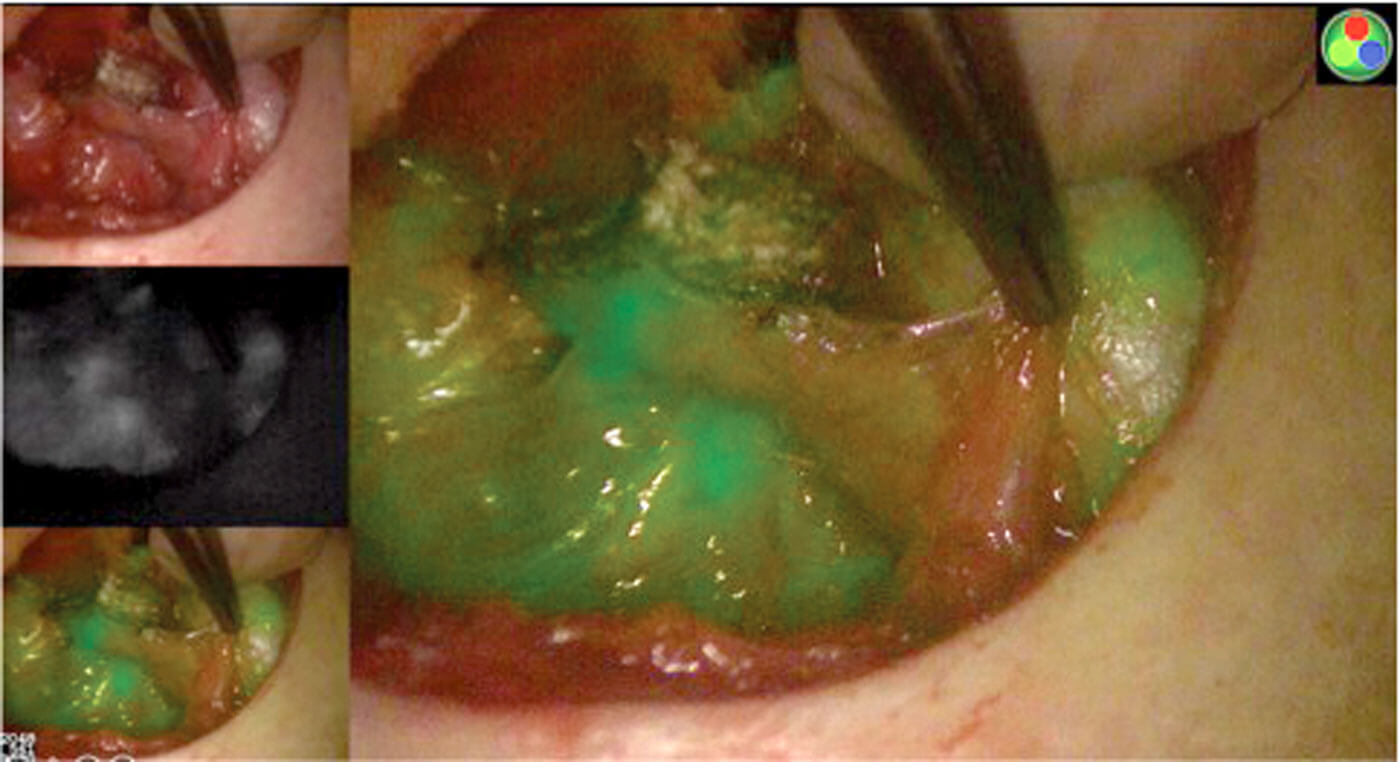

ICG being used to assess the vascularity of the parathyroid glands after thyroidectomy. Images show a very good blood supply to both parathyroid glands and therefore the patient is unlikely to have hypoparathyroidism. Top left: white light mode. Middle left: monochromatic mode displaying infrared signal. Bottom left/right: overlay of regular white light with ICG fluorescence in green. Images used with permission from Professor Frédéric Triponez.

Intraoperative injection of ICG to identify feeding vessel to aid with preservation.